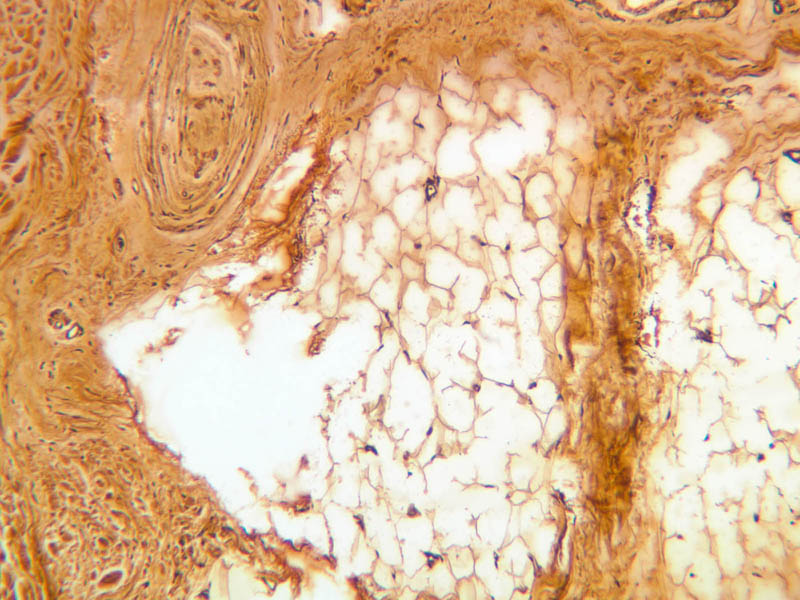

Deep pressure receptors known as Pacinian corpuscles also occur in the skin, as well as other sites (A-57 [2.5x-labeled, 10x, 20x, 40x-labeled] [2.5x, 10x, 20x, 40x-labeled]; A-50 [2.5x, 10x, 20x, 40x]). The sectioned appearance of the Pacinian corpuscle resembles a slice of onion, consisting of numerous concentric layers of tissue. Nerve endings generally thought to be responsible for pain sensation occur as bare fibers within the epithelial layers of skin epidermis, but these are not apparent in routinely stained sections (A-57, fingertip, Sevier Ag [10x, 20x, 40x] [10x, 20x, 40x] [20x, 40x] [20x, 40x]).

3 Pacinian Corpuscle PC Ag a57 pacinian corpuscle fingertip skin 2x ag labeled.jpgA57, Fingertip, 2.5x

4 Nerve Ending N Ag a57 pacinian corpuscle fingertip skin 40x ag labeled.jpgA57, Fingertip, 40x

5 Blood Vessel BV Ag a57 pacinian corpuscle fingertip skin 40x ag labeled.jpgA57, Fingertip, 40x

6 Lamellae (Concentric) L Ag a57 pacinian corpuscle fingertip skin 40x ag labeled.jpgA57, Fingertip, 40x

7 Lymph-like Fluid Ly Ag a57 pacinian corpuscle fingertip skin 40x ag labeled.jpgA57, Fingertip, 40x

8 Schwann Cell Nuclei SS Ag a57b pacinian corpuscle fingertip skin 40x ag labeled.jpgA57, Fingertip, 40x